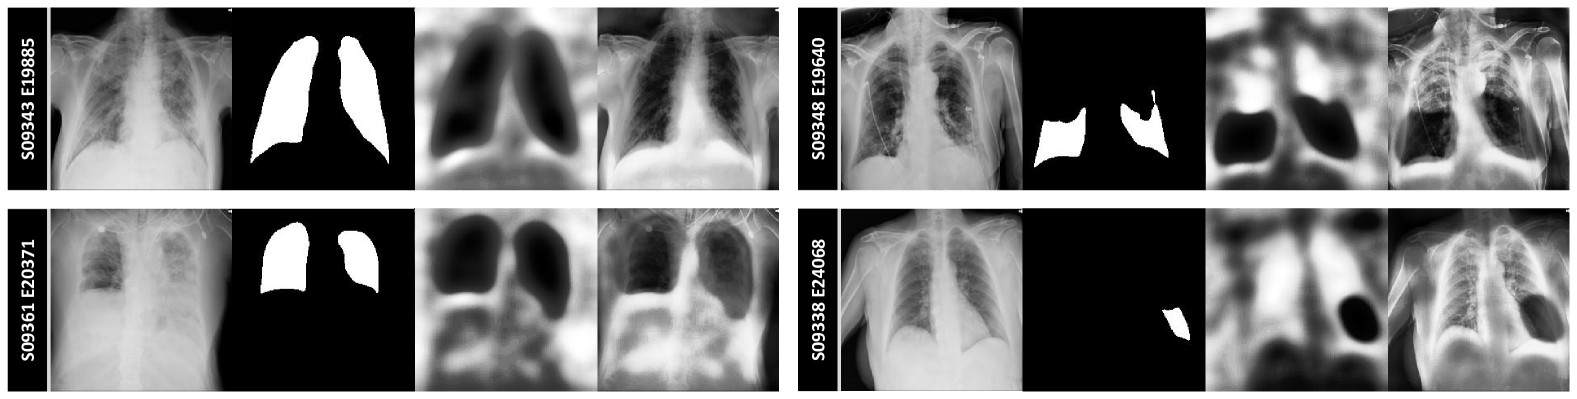

To evaluate the SGSeg framework’s efficacy, comparative analyses were conducted with current uni-modal and multi-modal segmentation models, as shown in table 1. Results illustrate that SGSeg exceeds the performance of conventional uni-modal methods and closely matches that of advanced multi-modal approaches. Relative to the leading uni-modal inference model, our approach achieved a notable enhancement in accuracy from 0.950 to 0.971 (2.21%percent2.212.21\%2.21 %), in the Dice coefficient from 0.8320.8320.8320.832 to 0.8740.8740.8740.874 (5.05%percent5.055.05\%5.05 %), and in the Jaccard index from 0.7240.7240.7240.724 to 0.7780.7780.7780.778 (7.46%percent7.467.46\%7.46 %). However, when compared with the top-performing multi-modal inference model, our method exhibited a slight decrease in accuracy by 0.41%percent0.410.41\%0.41 %, and reductions in the Dice coefficient and Jaccard index by 2.74%percent2.742.74\%2.74 % and 4.75%percent4.754.75\%4.75 %, respectively. Fig. 3 illustrated the significant impact of textual information on enhancing segmentation accuracy, particularly in challenging cases. It demonstrated that incorporating location-specific or pseudo-location data facilitates the model’s precision in identifying pathological areas. The SGSeg model was trained to identify lesions through weak supervision provided by additional textual data, compensating for the absence of textual descriptions at inference by autonomously generating this essential information. Consequently, the model leveraged guidance from the detector to achieve enhanced segmentation outcomes.

Refer to caption

Figure 3: Comparative Analysis of Segmentation Results: Uni-modal vs. Multi-modal Methods